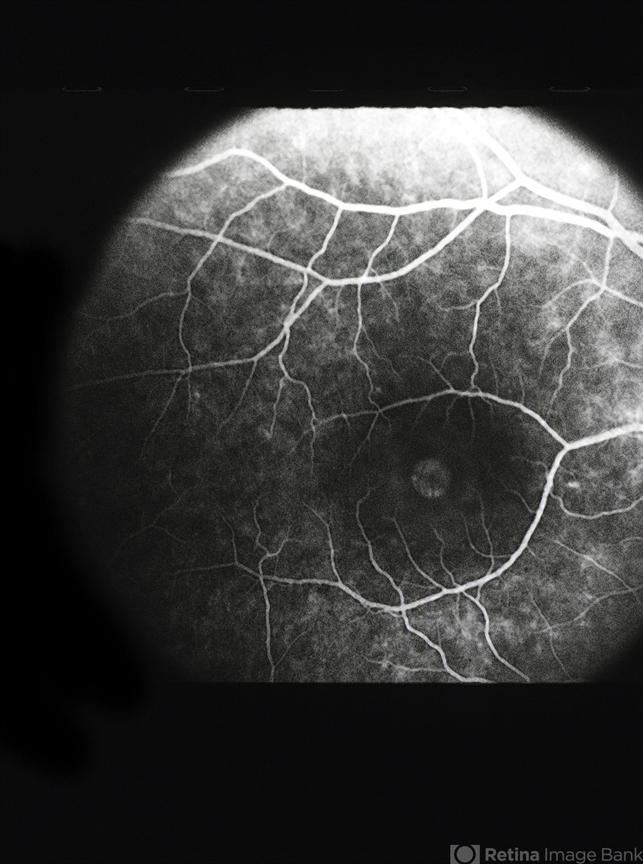

- macular hole

- The fluorescein angiogram of a macular hole demonstrates a round area of hyperfluorescence.